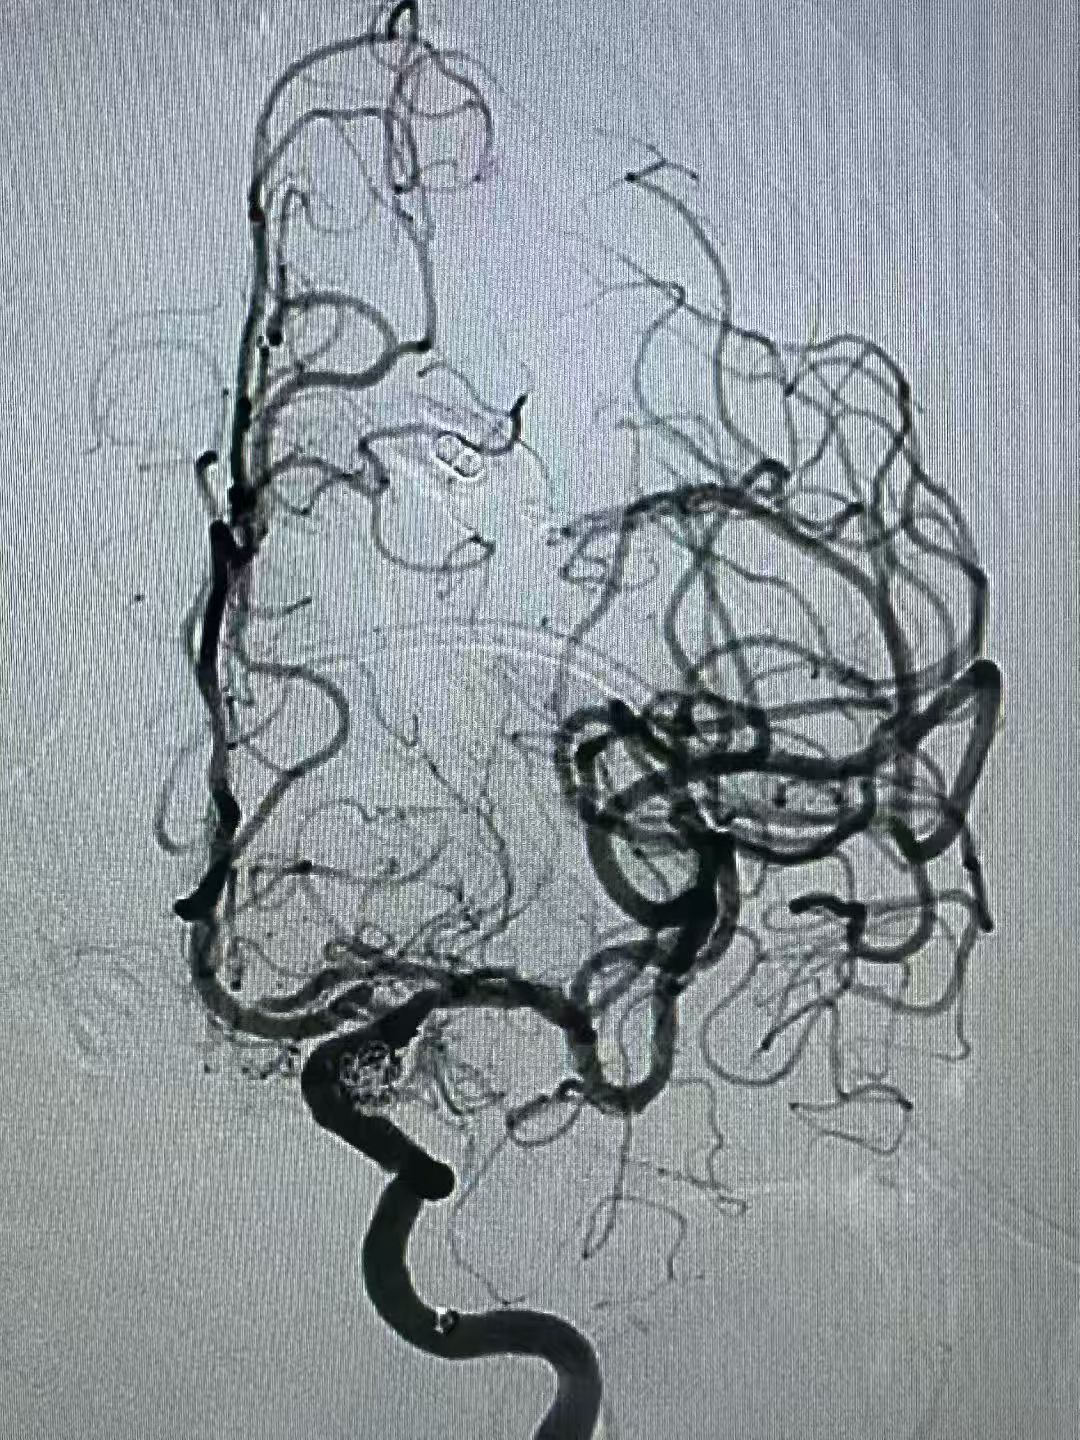

近日,桂平市中医医院脑病科介入团队成功为一例复杂颅内动脉瘤患者实施了微创介入手术。该手术采用了“弹簧圈联合血流导向密网装置”的先进技术,为患者解除了颅内“不定时炸弹”的威胁。此类高难度手术的成功开展,标志着我院在脑血管疾病的微创介入治疗领域具备了处理复杂病例的能力。 警惕隐匿的“脑内危机”:认识颅内动脉瘤 颅内动脉瘤并非肿瘤,而是颅内血管壁因局部薄弱而异常膨出的一个“小血泡”,其最大风险在于破裂出血。一旦破裂,致死致残率极高。临床上,动脉瘤在破裂前有时会因压迫邻近的神经而出现预警信号,如突发剧烈头痛、眼睑下垂、视物模糊等。 本例患者因“突发头痛伴左侧眼睑下垂”来院。经急诊脑血管造影(DSA)检查,确诊为左侧颈内动脉后交通段动脉瘤。该动脉瘤形态不规则、瘤颈宽大,治疗难度较高。若采用传统单一技术,可能面临诸多挑战。 微创介入:“双管齐下”的精准治疗策略 经过严谨的术前讨论评估,脑病科周辉主任团队为患者制定了“弹簧圈联合血流导向密网装置”的个体化手术方案。 与传统的开颅手术相比,该微创介入技术仅需通过大腿根部股动脉进行穿刺,利用一根极其精细的微导管,在数字减影血管造影机(DSA)的实时引导下,将装置精准输送至病变血管。手术团队首先将弹簧圈填入动脉瘤囊内,促进内部血栓形成;随后,将一张血流导向密网装置释放并覆盖于瘤颈开口处。该装置能有效引导血流主流远离动脉瘤,从而为动脉瘤的自然萎缩闭合创造条-件,显著降低远期复发风险。 在麻醉科、介入导管室的通力协作下,手术顺利完成。术后造影显示,动脉瘤栓塞效果满意,载瘤动脉通畅。患者术后恢复良好,次日即可下床活动,头痛症状缓解,神经功能得到改善。 学科进展:为复杂脑血管病患者提供更多选择 脑病科周辉主任介绍,“弹簧圈联合血流导向密网装置”技术是目前处理大型、巨大型、宽颈等复杂颅内动脉瘤的先进方案之一。这一技术的应用,拓展了微创介入治疗的适应范围,使得一些以往难以通过微创方式治疗或需行高风险开颅手术的患者有了新的选择。 健康提示:早筛早诊是关键 颅内动脉瘤多为隐匿发生。建议有高血压、高血脂、长期吸烟、有脑血管病家族史等高危人群,应重视脑血管健康筛查,做到早发现、早诊断、早治疗。切勿忽视突发性剧烈头痛、眼睑下垂等身体发出的“预警信号”。 桂平市中医医院脑病科始终致力于追踪和应用前沿技术,以专业的医疗团队和丰富的临床经验,为百姓的脑血管健康保驾护航。 健康咨询 健康咨询电话 0775—3384702 0775—3372569 门诊地址 桂平市中医医院 2号楼3楼366诊室 住院地址 桂平市中医医院 1号楼7楼、2号楼7楼 |